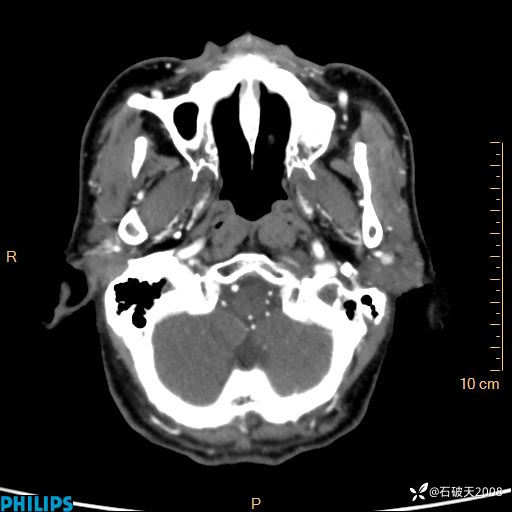

平扫